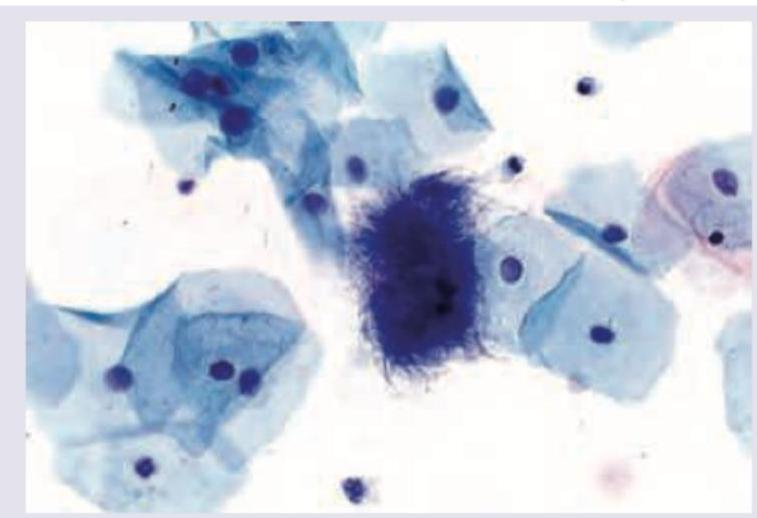

Name the cell shown in the Pap smear image.

Explanation: ***Koilocyte*** - A **koilocyte** is a squamous epithelial cell that has undergone a series of structural changes, indicative of **human papillomavirus (HPV) infection** [1][2]. - Key features include a **perinuclear halo** (a clear zone around the nucleus), a **hyperchromatic nucleus** (darkly stained nucleus), and often a slightly irregular nuclear membrane [1][2]. *Superficial cells* - These are mature squamous cells with a **small, pyknotic nucleus** (dense and dark) and abundant, transparent cytoplasm [1]. - They are typically seen in the later stages of the menstrual cycle and do not show the characteristic perinuclear halo of koilocytes. *Intermediate cells* - These are polygonal or oval-shaped squamous cells with a **larger, vesicular nucleus** (less dense) than superficial cells and a moderate amount of cytoplasm. - They are common throughout the menstrual cycle but lack the specific nuclear and cytoplasmic changes associated with HPV infection. *Trichomonas infection* - While **Trichomonas vaginalis** can be identified in a Pap smear, it appears as pear-shaped flagellated protozoa, often associated with a "dirty" background due to inflammatory cells and cellular debris. - It does not present as a specific cell type like a koilocyte, but rather as an infectious agent. **References:** [1] Kumar V, Abbas AK, et al.. Robbins and Cotran Pathologic Basis of Disease. 9th ed. The Female Genital Tract, p. 1010. [2] Kumar V, Abbas AK, et al.. Robbins and Cotran Pathologic Basis of Disease. 9th ed. The Female Genital Tract, pp. 1008-1010.